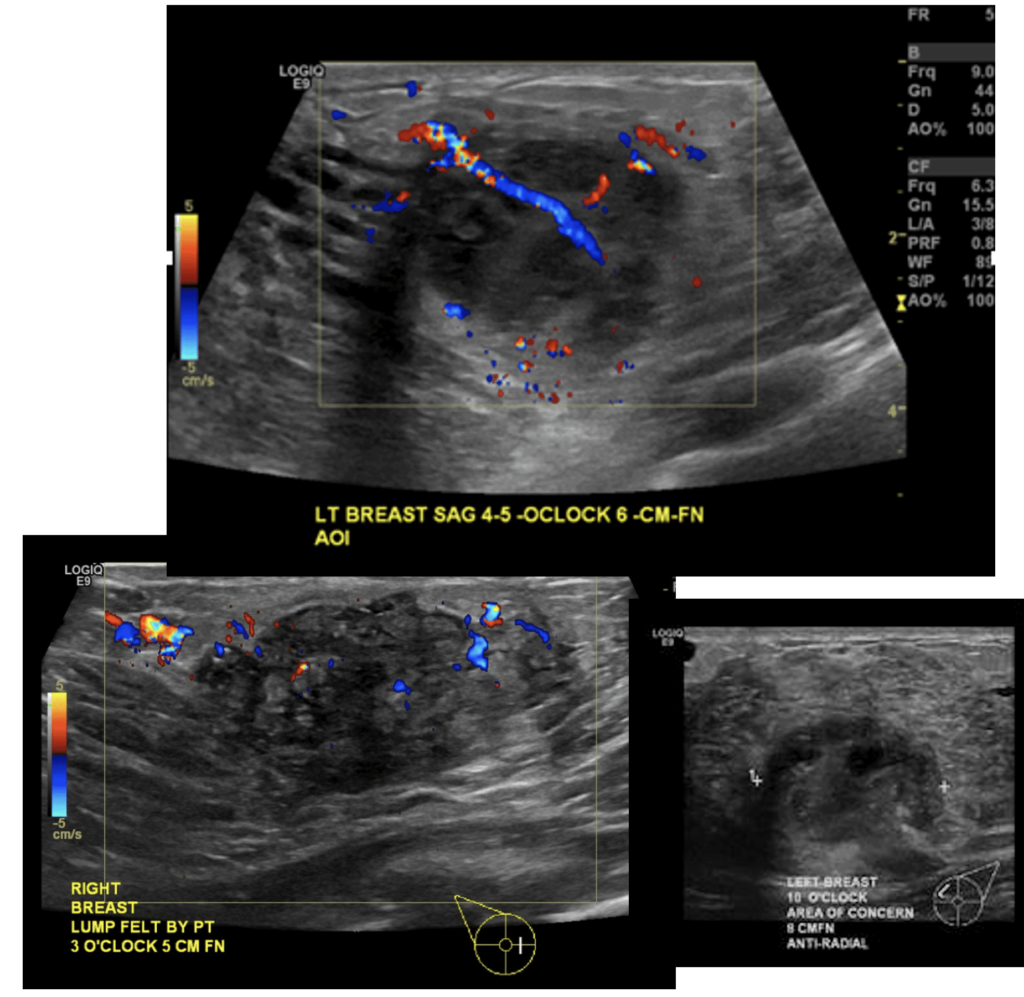

A phlegmon is an indistinct area of tissue inflammation, fluid collection, and inflamed capillaries (blood vessels). It can present with redness overlying the area of massage or it can present with a mass-like area in the breast. Ultrasound should confirm the difference between a phlegmon and an abscess (which is a fluid collection that requires drainage).